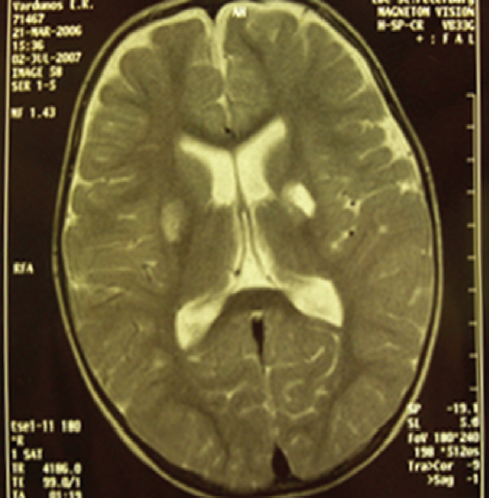

Materials and methods. 100 children with purulent meningitis were examined, aged from 1 to 17 years 11 months, for the period since 2007 to 2020. All patients underwent neurological monitoring, etiological verification of diagnoses, determination of markers of endothelial dysfunction in the blood (D-dimer and desquamated endothelial cells), as well as MRI of the brain and MRI angiography.

Results. A complex lesion of the vascular system in purulent meningitis in children was proved, associated with both structural and functional properties of the vascular wall, as well as damage to the vasomotor function of the endothelium.

Conclusions. With purulent meningitis, there is damage to the vascular bed in the form of systemic vasculitis, including cerebral vessels, as evidenced by the presence of both markers of endothelial damage (desquamated endothelial cells and D-dimer) and changes in MRI and MRI angiography.